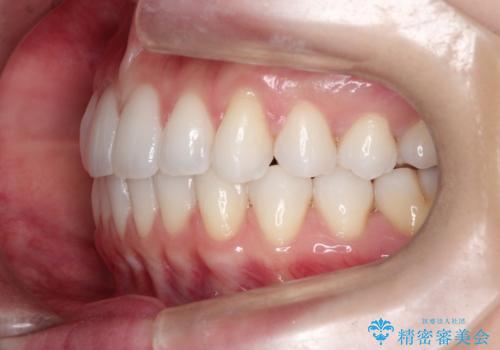

- 主訴:「右上犬歯を引っ込めて、歯並びをキレイにしたい」

右上の八重歯を気にされてご来院されました。結婚式を控えていたため挙式にまでに可能な限りキレイにしたいとのことでした。

右上の犬歯の歯茎は矯正前から退縮を起こしていましたが、矯正後もその退縮に関しては変化がありませんでした。今回は患者様が歯肉退縮に関しては治療をご希望ではありませんでしたが、当院ではこのように歯茎が下がり露出した根面を、歯茎を移植することでカバーし見た目を改善する手術を行っています。